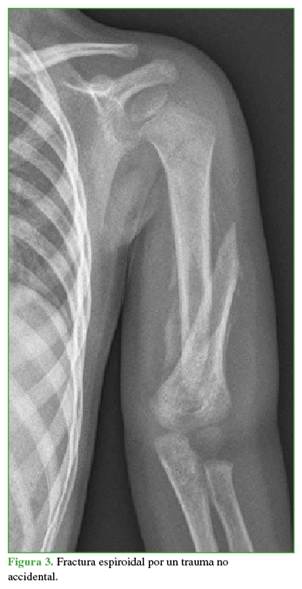

6.       Las fracturas humerales supracondíleas en niños se asocian con lesiones accidentales, mientras que las fracturas humerales por abuso más comunes en niños <5 años son las espirales u oblicuas (Figura 3).

7.       Las fracturas de húmero en niños <18 meses se asocian más con el abuso que las fracturas humerales en niños mayores.